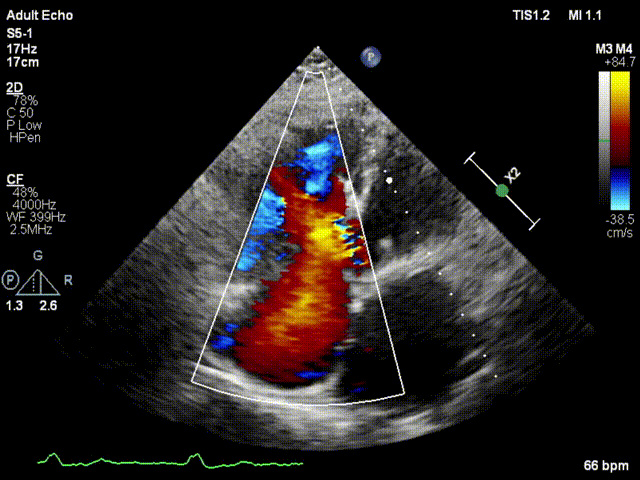

本次接受治療的患者是一名74歲的女性,14年前因風(fēng)濕性心臟病行二尖瓣生物瓣植入術(shù),合并房顫。近3年來反復(fù)因腹脹、納差、下肢水腫入院,藥物治療欠佳。心臟超聲顯示三尖瓣極重度反流(有效反流口面積:0.76cm²,反流容積:79ml),繼發(fā)性右房室增大及上、下腔靜脈增寬(右房上下徑*左右徑:52*41mm,右室左右徑:46mm,下腔靜脈:29mm),右室收縮功能正常,肺動(dòng)脈收縮壓 43mmHg,左心室射血分?jǐn)?shù)73% ?;颊呒韧_胸手術(shù)史,術(shù)前評(píng)估STS 評(píng)分為7.02分,CRS 9分,無法接受體外循環(huán)下三尖瓣外科手術(shù)。面對(duì)這一傳統(tǒng)治療無法解決的困境,葛均波院士及其團(tuán)隊(duì)周達(dá)新教授、潘文志教授、張?jiān)床┦?、陳莎莎博士及心超室的潘翠珍教授、李偉教授?jīng)過討論決定,采用創(chuàng)新的Lux-Valve Plus系統(tǒng)為患者進(jìn)行經(jīng)血管三尖瓣置換。

手術(shù)在患者全麻狀態(tài)下進(jìn)行,采用經(jīng)右側(cè)頸靜脈作為入路,將裝載有人工瓣膜的輸送器緩慢推送至右心房;并在經(jīng)食道超聲和DSA的引導(dǎo)下小心調(diào)整輸送器角度,將輸送器送入右心室;逐步釋放瓣膜錨定裝置和盤片,調(diào)整瓣膜位置后,錨定瓣膜完成植入。術(shù)后右房壓明顯下降,從術(shù)前的25/10(16) mmHg降至術(shù)后即刻的12/7(10) mmHg,術(shù)后超聲提示人工三尖瓣同軸性良好,固定牢固,無反流及瓣周漏,手術(shù)室即刻拔除氣管插管。